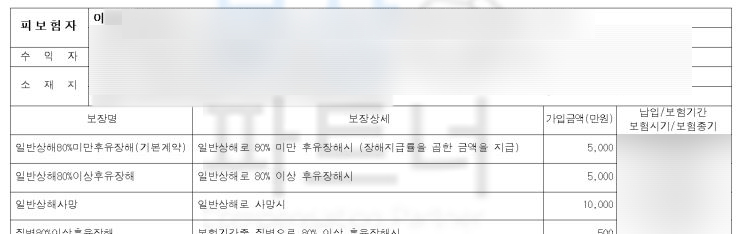

이@@님의 보험증권에는 상해후유장해 3-100% 일반상해80%미만후유장해(기본계약) 일반상해후유장해보험금 등등 모두 표기된 것은 다르지만

“장해”를 보장해주는 담보에 가입되어 있으셨습니다.